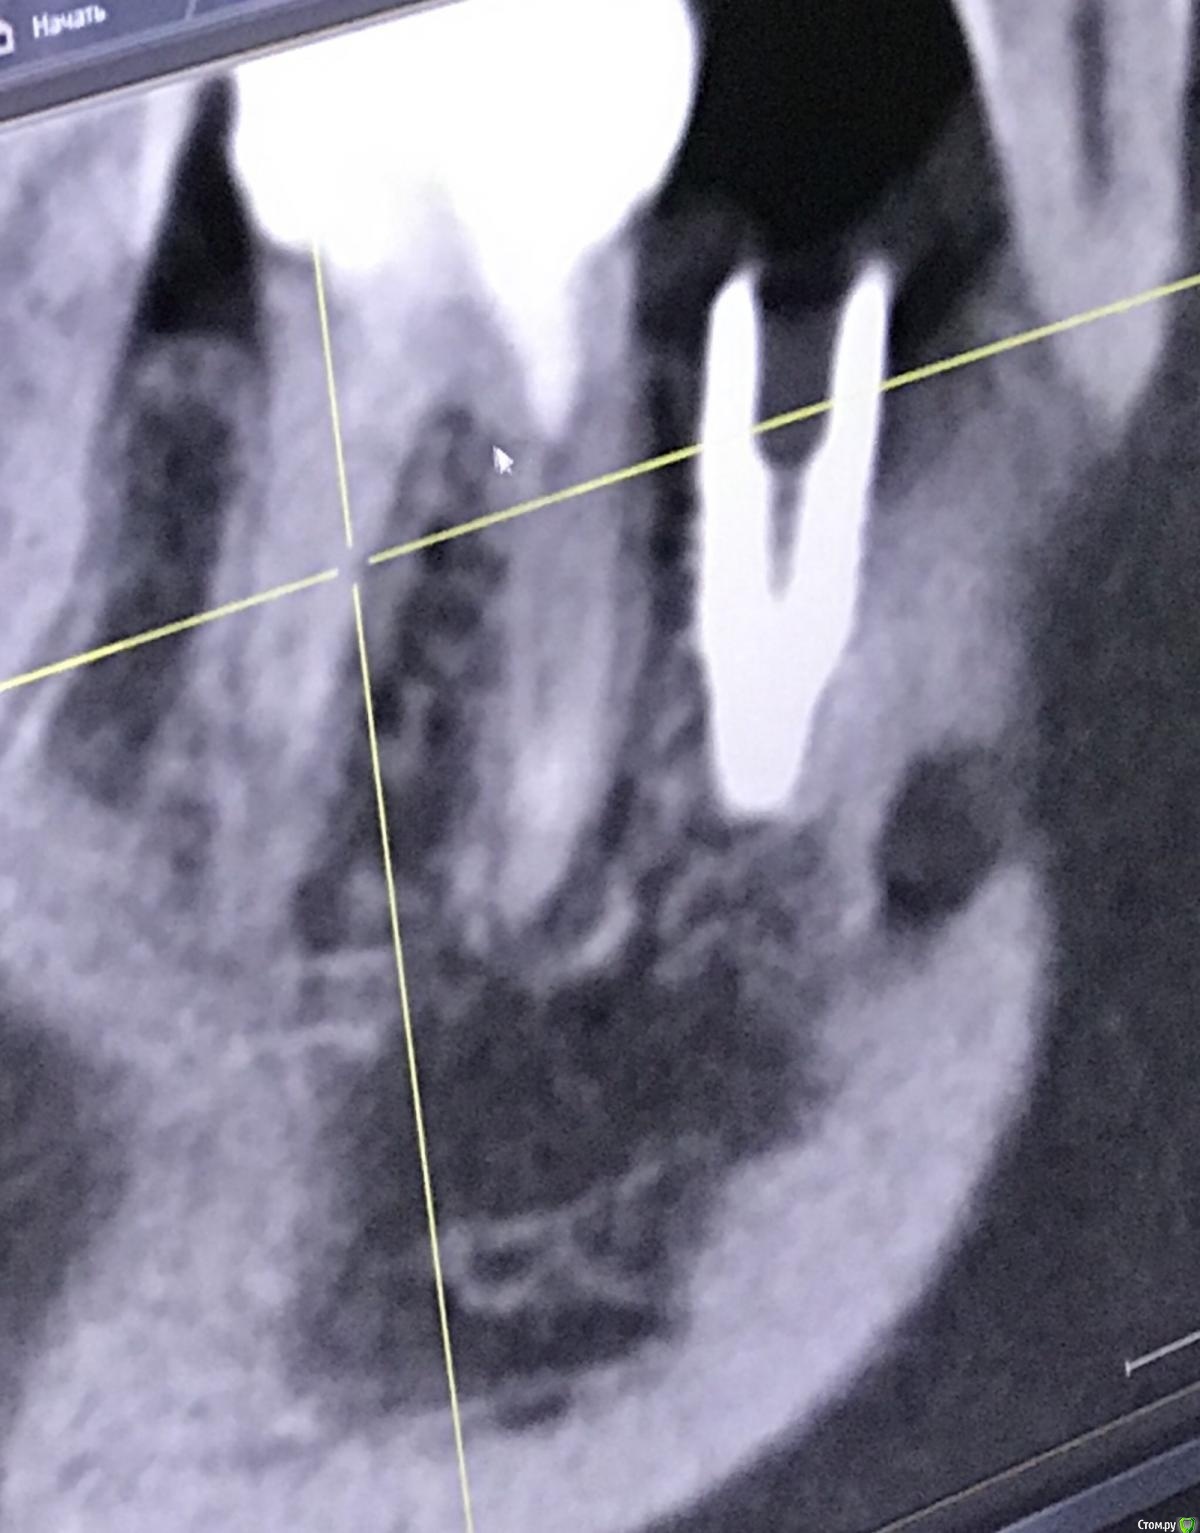

Irouil Опубликовано 26 декабря, 2020 Поделиться Опубликовано 26 декабря, 2020 Имплант запротезирован? Когда был установлен? Маловероятно, что описываемые жалобы связаны с имплантатом. Скорее причина в зубе - решение о его лечении лучше спросить в терапевтическом разделе, хирурги зубы не лечат. Если имплантат не запротезирован, то мне кажется логичнее его удалить - очень комрромиссно придется протезировать. Если уже есть коронка - нужен рентген с ней. 1 Ссылка на комментарий

111 Опубликовано 26 декабря, 2020 Автор Поделиться Опубликовано 26 декабря, 2020 (изменено) Iroil, спасибо большое за ответ.46 был кариес но не болел, периодонтита не было, никаких воспалений на верхушках не было. То есть 46 просто пролечили - обработали каналы, заложили кальций, и тд. Делалось под микроскопом, доктор очень хороший. По поводу 45 - изначально кости было достаточно по высоте, по объему пришлось подсыпать gen-oss 0,5 в момент имплантации, плюс сст с бугра. Вообще всё было хорошо, особо сильно не болело, без отёка зажило. В момент снятия швов - обнаружилась убыль кости в области 46, слегка оголился корень ближайший к 45, но мы как-то это не обсуждали с доктором. Установили Фдм, все ок.И вот пришло время ортопедии - это было летом 2019 - ортопед не захотел работать с имплантом, у которого на снимке оголена шейка. Десны достаточно при этом. Имплант не запротезирован.Спустя пару дней на визите у хирурга - я прошу выкрутить 45, мне отказывают, принято решение либо оставить как есть, либо подсыпать кости немного.Сейчас, декабрь 2020, я хожу с фдм и уже точно понимаю, что надо переустановить 45, но хирург предлагает 2 варианта:- оставить как есть и делать ортопедию (т.к. десна хорошая);- удалить 45 и 46 для создания удобного рабочего поля и имплантация 45, 46.Вот я пытаюсь понять, нельзя ли просто 45 выкрутить? Аккуратно удалить 45 не получится? (Очень не хочется расставаться с 46, сам по себе он не болит при накусывании и постукивании). Изменено 26 декабря, 2020 пользователем 111 Ссылка на комментарий

Irouil Опубликовано 26 декабря, 2020 Поделиться Опубликовано 26 декабря, 2020 Не вижу явных причин удалять зуб. Удалять зуб ради удаления имплантата - такого ещё не слышал 1 Ссылка на комментарий